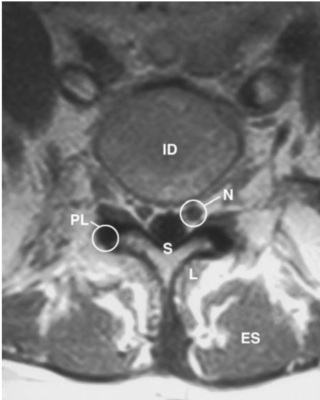

Cột sống thắt lưng

Các chữ viết tắt:

- A = L2 vertebral body; thân đốt sống L2

- B = L3/4 disc space; khoảng đĩa đệm L3/4

- C = Spinous process; mỏm gai

- D = Transverse process; mỏm ngang

- DG = Dorsal root ganglion of L2 in intervertebral foramen

- E = Sacroiliac (S–I) joint; Khớp cùng -chậu

- ES = Erector spinae muscle; cơ dựng gai

- F = Articular facet; Diện khớp nhỏ

- ID = Intervertebral disc; đĩa đệm

- L = Lamina of vertebral arch; bản cung

- L5 = L5 vertebral body; thân đốt L5

- N = Nerve root; Rễ thần kinh

- PI = Pars interarticularis; Phần liên mỏm khớp (eo)

- PL = Pedicle; cuống cung

- S = Spinal canal, cauda equina (C); ống tuỷ, đuôi ngựa

- SI = Sacroiliac joint; Khớp cùng chậu

- V =Vertebral body; Thân đốt sống